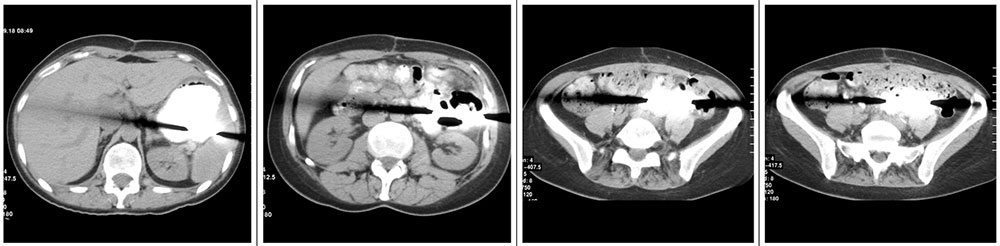

Case 9  49 year old woman status post cytoreductive surgery 2 weeks prior. IV contrast enhanced CT shows:

Case 9  49 year old woman status post cytoreductive surgery 2 weeks prior. IV contrast enhanced CT shows:

Retained Metal Malleable Retractor